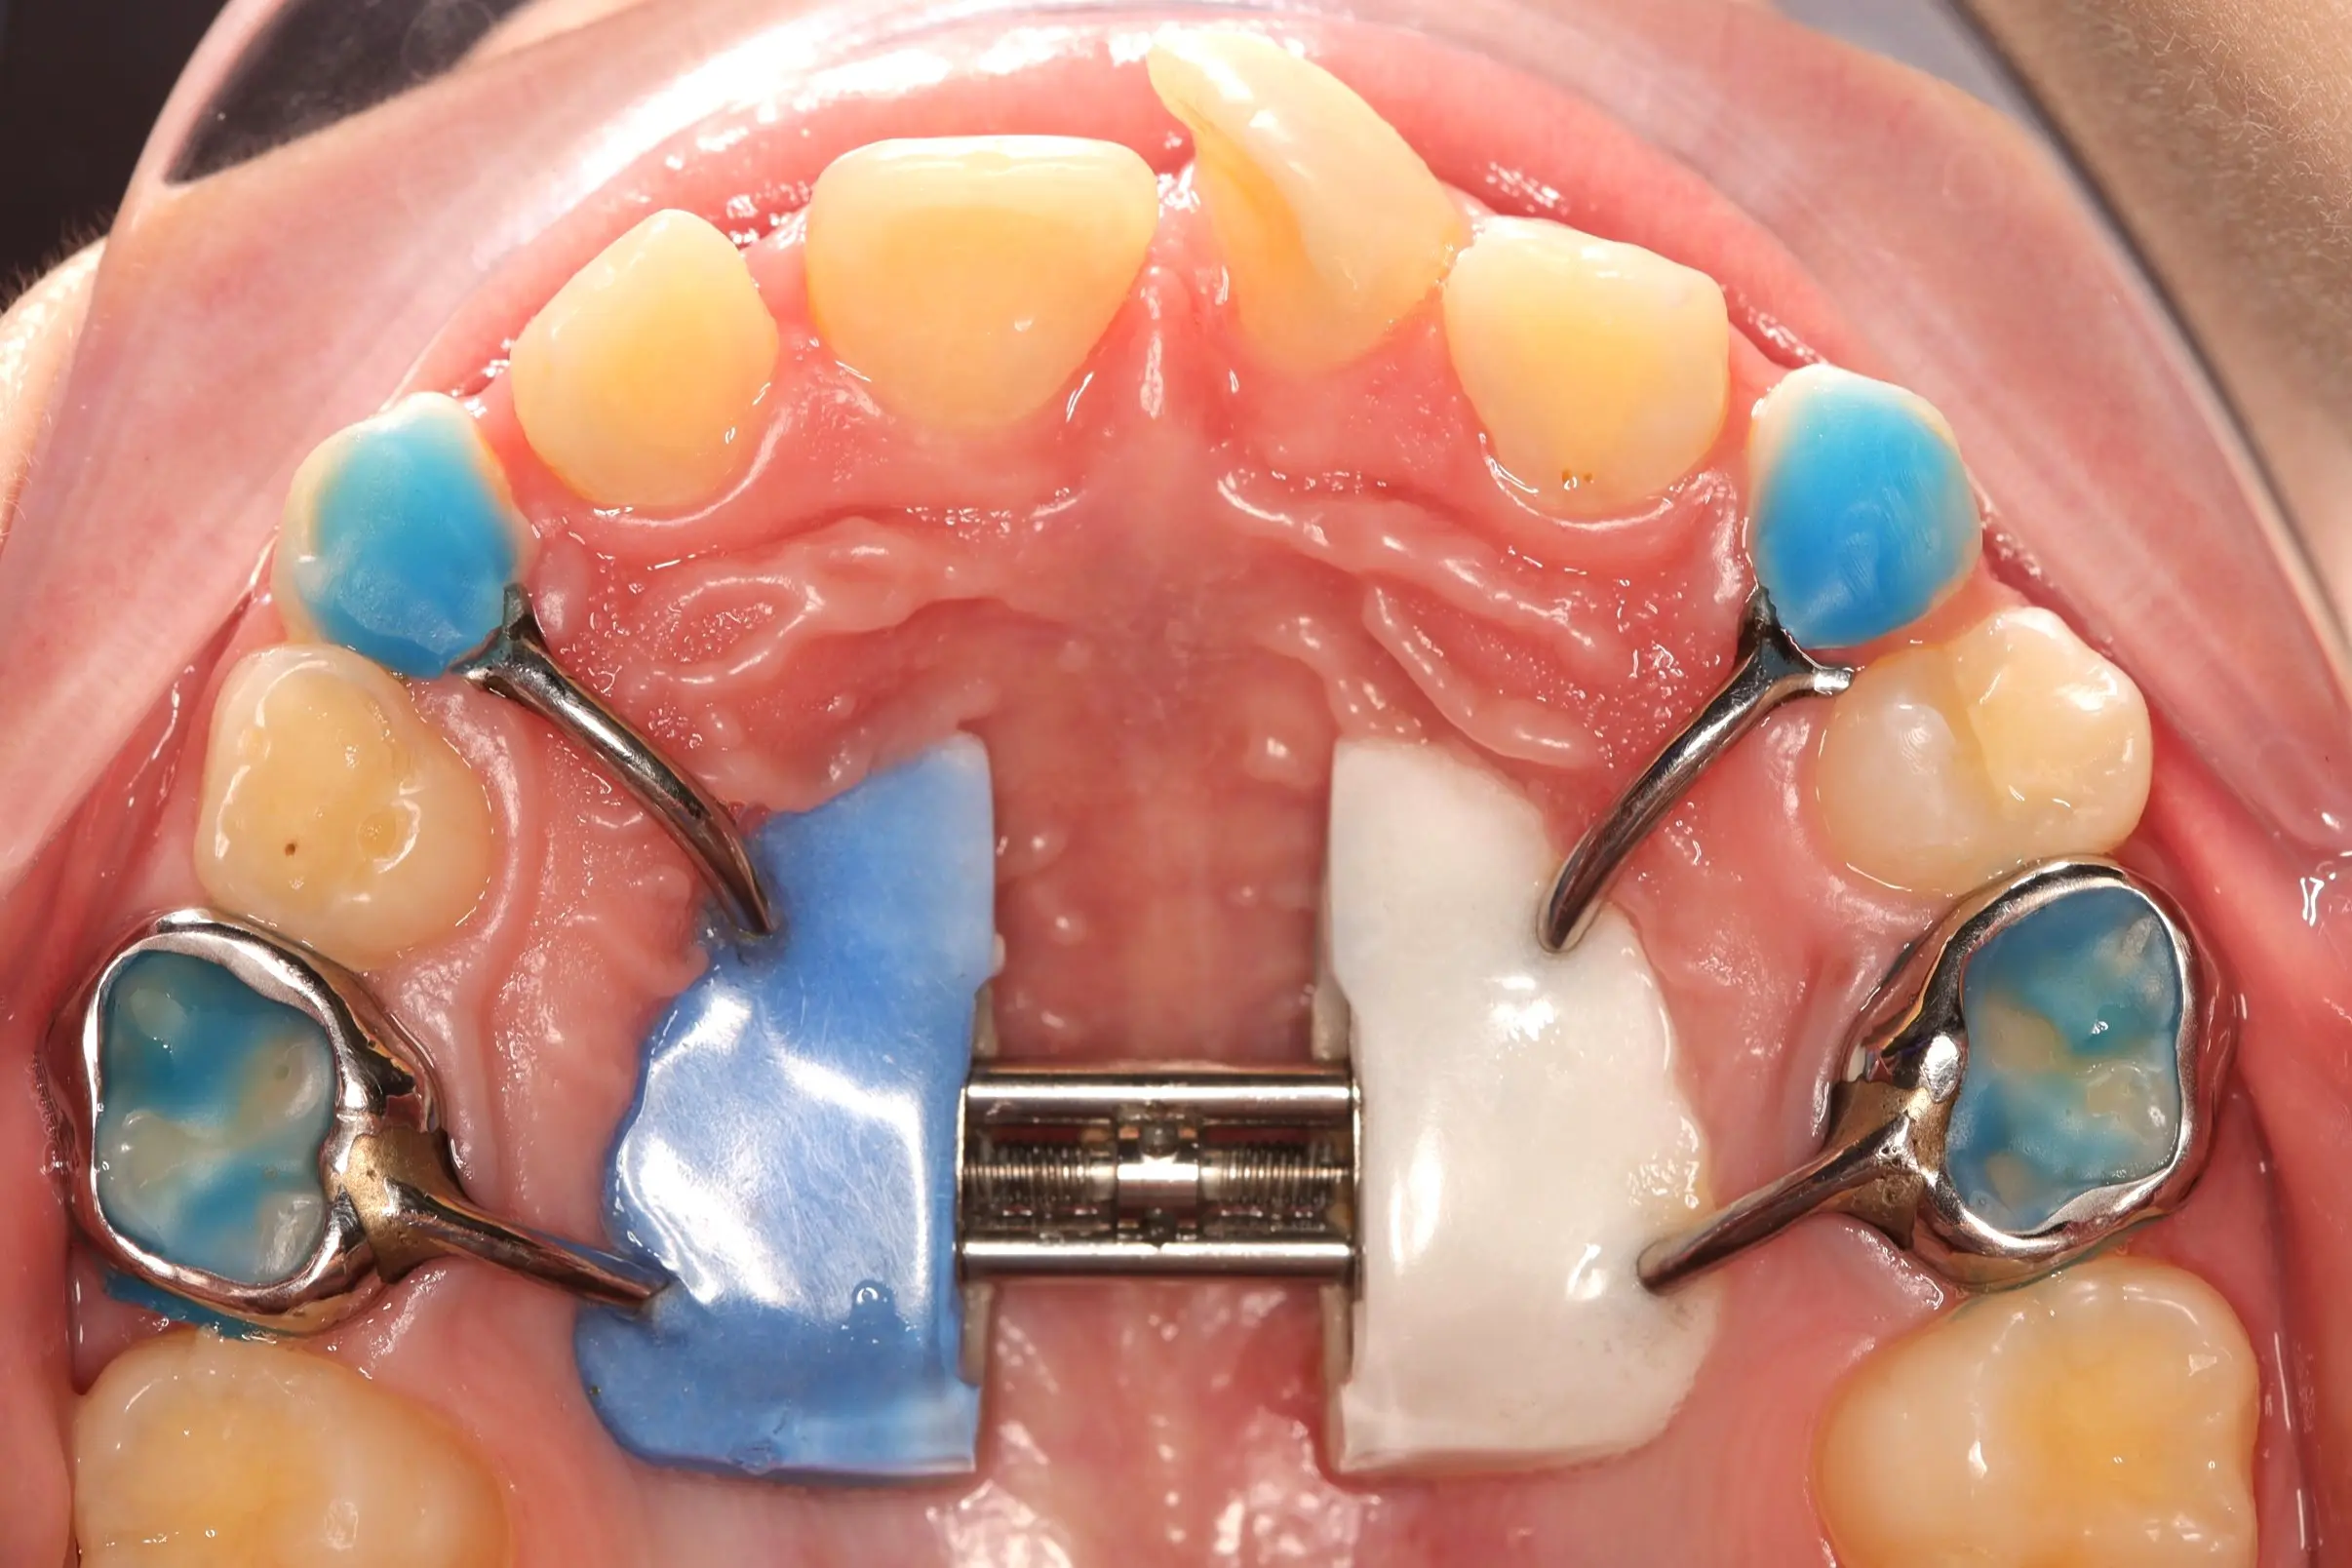

Лікування розпочато з розширення верхньої щелепи за допомогою незнімного апарату Marco Rosa, що дозволило сформувати необхідний простір. Далі проведена корекція положення різців із використанням часткової металевої брекет-системи 2х4, яка забезпечує точний контроль навіть на ранніх етапах формування прикусу.

Такий комбінований підхід дає можливість:

- створити достатній простір для зуба

- правильно зорієнтувати різці в зубному ряді

- запобігти більш складному лікуванню в майбутньому